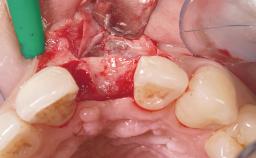

Immediate Flapless Placement of an Implant in a Maxillary Left Central Incisor Site

A 29-year-old female patient presented for treatment to replace the upper left central incisor tooth with an implant- supported restoration. The tooth had been intermittently symptomatic for the previous 12 months. The tooth had originally suffered trauma about 15 years previously. Several endodontic treatments had been performed, including an apicectomy procedure to retain the tooth. The patient was healthy and a non-smoker. She had reasonable expectations in regard to esthetic outcomes and the risk of marginal tissue recession following treatment. At medium smile, the gingival margins of the upper teeth were visible, with a display of 3 to 4 mm of the gingival margins. Gingival recession of tooth 21 and a discrepancy in the gingival levels between teeth 11 and 21 was observable during normal speech and smile.

Soft Tissue Anatomy Intact Defective

Soft Tissue Contour and Volume Slightly compromised